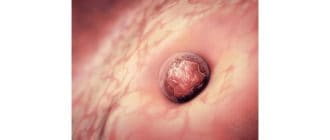

移植滲出は、受精卵が女性の子宮の内面に付着して妊娠の成長過程を開始するときに起こります。 それは妊娠中の女性には普通の出来事ですが、多くの女性はそれが何であるかを完全に認識していません。 いくつかの女性は、出血を月経から […]